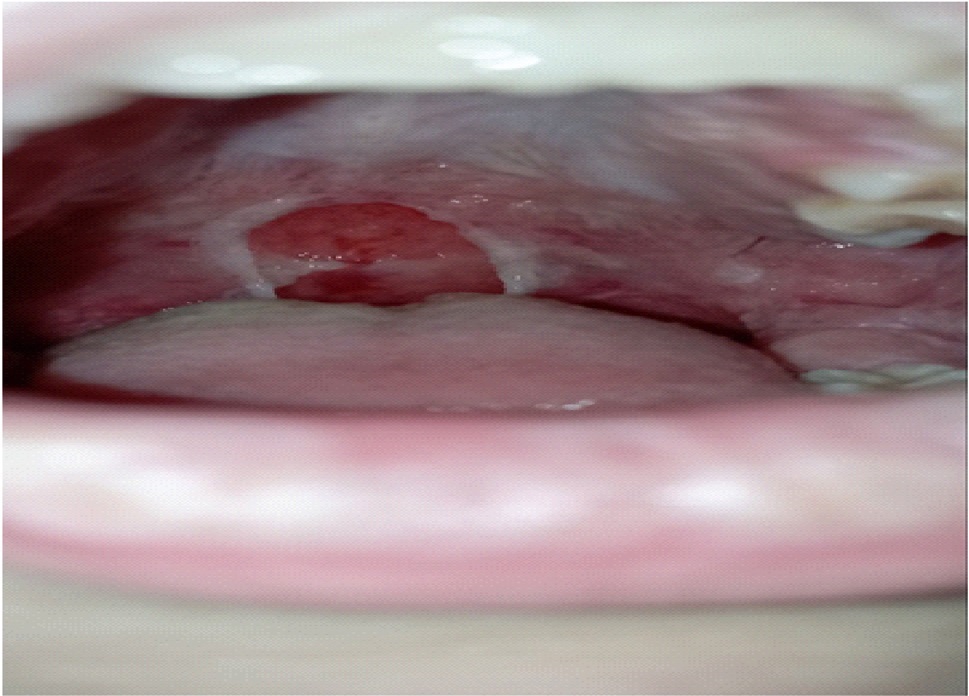

При поступлении состояние ребенка средней степени тяжести. Наблюдается фебрильная температура, частый малопродуктивный кашель. На кожных покровах в области лучезапястных суставов, живота отмечается макулопапулезная сыпь с умеренным кожным зудом. Слизистая ротовой полости ярко гиперемирована, на твердом небе множественные афты белого цвета, слизистая губ покрыта язвами с гнойным отделяемым, наблюдается хейлит (рис. 2).

Рис. 2. Мукозит с поражением слизистой оболочки рта: денудация слизистой (9-й день болезни)

Примечание: фото авторов.